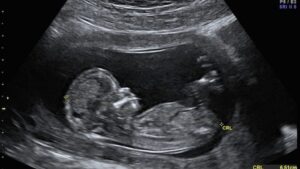

УЗИ первый триместр беременности — первая возможность увидеть маме будущего малыша в период беременности. Необходимо соблюдать все рекомендации медиков, чтобы период вынашивания плода закончился благополучно.

Первое УЗИ позволяет установить наличие внематочной беременности, дает представление о перспективах и сроках развития плода.

- КТР – исследование размеров.

- БПР – окружность головы.

- Симметричность полушарий мозга.

- Работа сердца.

- Параметры костей конечностей, предплечий, бедер.

Все базовые данные можно собрать практически сразу. Рост эмбриона составляет 3-7 см. Утолщение на шее не более 3,1 мм.